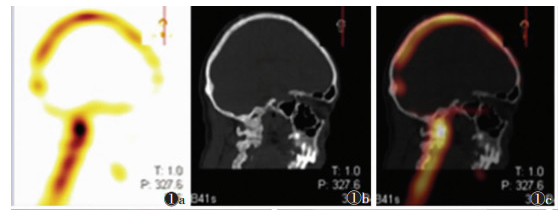

2 结果49例共91处疼痛部位,发生于颅骨颈椎(图 1)、肋骨、髋关节(图 2)、骶髂关节(图 3)、胸椎(图 4)等处的疼痛较剧烈且为持续性疼痛,夜间更明显,并随时间推移逐渐加重,常规非甾体药物缓解不明显。SPECT/CT融合断层显像示阳性40处,其中真阳性35处,假阳性5处;阴性51处,其中真阴性49处,假阴性2处。SPECT/CT融合断层显像对肿瘤疼痛骨转移瘤诊断的敏感度为94.6%(35/37)、特异度为90.7%(49/54)、准确率为92.3%(84/91)。后经病理及临床随访证实5处假阳性病灶中3处为退行性病变,由于存在隐匿性骨质破坏导致骨代谢增高,核素浓聚;余2处,1处为髓腔炎症所致,1处为原发骨肿瘤。2处假阴性病灶由于病灶体积较小,1处位于胸椎重叠部位,1处示溶骨性改变,最后融合显像显示放射性浓聚不明显而导致漏诊。

| 图 1 男,72岁,前列腺癌骨转移,颈椎持续性疼痛 图 1a SPECT/CT局部融合显像示:颅骨、颅底部、上颈椎可见小片状放射性核素浓聚区 图 1b 颅骨CT平扫示:颅骨板障密度增高,髓腔皮质边界模糊,颅骨密度不均匀,双侧蝶骨、下颌骨、寰椎、枢椎均可见斑片状密度增高影。右侧上颌窦内可见类圆形密度增高影 图 1c SPECT/CT局部融合图像示:颅骨、颅底部可见小片状放射聚集区,上颈部可见高放射性核素聚集 |